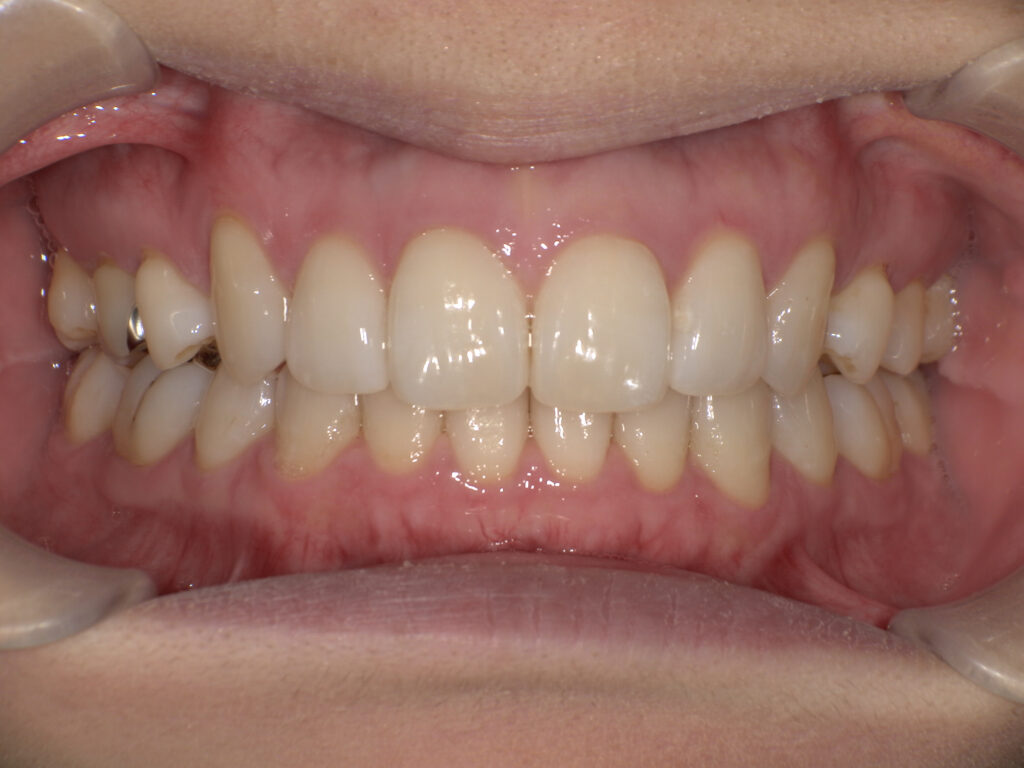

【マウスピース矯正】

矯正前(正面・側貌)

矯正後(正面・側貌)

主訴すきっ歯

初診年齢38歳

治療内容、装置アライナー

抜歯、非抜歯非抜歯

治療期間8ヶ月

費用473,000円

(相談料、検査料、診断料、動的治療費、保定期間料を含む)

治療のリスク、副作用歯の移動に伴う痛み

上下顎前歯部の歯根吸収

ブラッシング不良によるむし歯、歯周炎